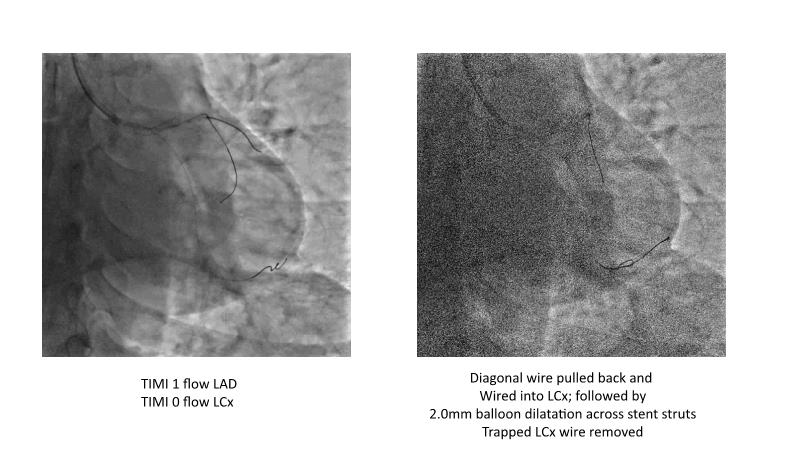

This session is recommended for you if you are seeking insights into the advantages of using IVUS imaging over visual assessment for better outcomes in left main bifurcation procedures. Discuss with experts the benefits of using RotaCUT in lesion preparation for left main bifurcation and explore the impact of high radial strength stents on the procedure's success.

• To know how a high radial strength stent can make a difference in left main bifurcation